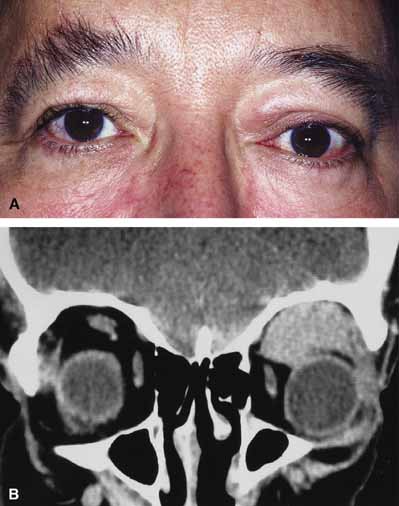

ORBITAL CELLULITIS Orbital cellulitis is the model for acute inflammation and a major cause of orbital inflammation in adults.2 It is characterized by a rapid development (over 1 to 2 days) of inflammatory signs and symptoms. These include: eyelid swelling, redness, warmth, pain, conjunctival injection, chemosis, proptosis, and mobility impairment with or without reduced vision. These patients generally feel unwell (malaise) and are febrile (Fig. 1A and 1B). The malaise and fever are key features in differentiating cellulitis from a rapid-onset nonspecific orbital inflammation (pseudotumor) and should be obtained from the patient's history. The majority of orbital cellulitis is secondary to extension from an adjacent sinus infection (Fig. 1C). Organisms gain access to the orbit directly through the thin ethmoidal bone, through congenital or acquired dehiscences in the thin orbital walls, pass through preexisting orbital foramina, pass retrogradely through the valveless venous orbital system, or along the veins as a periphlebitis. Orbital cellulitis may also be secondary to an endophthalmitis, systemic bacteremia (e.g., after dental work), infection of a nearby skin wound, dacryocystitis, or penetrating trauma. The history and physical examination are crucial in distinguishing between preseptal and true orbital cellulitis. The orbital septum delineates the anterior eyelid soft tissue from the orbital soft tissue. Infections anterior to the septum are classified as preseptal cellulitis while those posterior to the septum are termed orbital cellulitis. Recognition of true orbital involvement is important not only because of the threatened visual loss associated with the orbital involvement but also because of the potential for central nervous system complications including cavernous sinus thrombosis, meningitis, and death. Preseptal cellulitis is characterized by lid edema, erythma, and discomfort. Inflammation posterior to the orbital septum (orbital cellulitis) is heralded by the development of pain, chemosis, proptosis, motility disturbance, and visual deterioration. The extent of ocular involvement in preseptal and orbital cellulitis can be determined by assessing visual acuity, extraocular motility, pupillary reaction, color vision, confrontation visual fields, intraocular pressure, and optic nerve head appearance. Evidence of facial/head trauma or surgical wounds may be apparent. Constitutional signs such as fever, lethargy, and irritability should be sought. The examiner should assess for meningeal signs and neurologic defects. After the initial examination, the physician should follow patients with orbital cellulitis with at least daily assessments of visual acuity, motility, and pupil reaction. Progression of the disease process despite appropriate antibiotic therapy suggests abscess formation. Orbital abscesses may be either localized, diffuse, or subperiosteal (Fig. 1C). Subperiosteal abscesses most commonly occur along the medial wall and may expand rapidly, compromising optic nerve function even in the absence of many signs of infection.3–6 Several mechanisms may contribute to visual deterioration including direct optic nerve compression, elevation of the intraorbital pressure, and proptosis causing a “stretch” optic neuropathy. Clinically, the eye typically is displaced away from the subperiosteal abscess, and orbital imaging shows a convex mass adjacent to the involved sinus. Orbital infection with potential orbital abscess formation occurs when bacteria break through the periorbita and gain access to the extraoconal or intraconal space. Diffuse or localized orbital abscess formation may also lead to visual loss through an increase in intraorbital pressure, posterior ischemic optic neuropathy, optic nerve inflammation, or vasculitis. Acute visual loss in the presence of an orbital infection is almost always a surgical emergency in which immediate drainage of the abscess is required to save vision. Continued posterior extension of the infection may result in an orbital apex syndrome, decreased function of cranial nerves,2–6 thrombosis of the cavernous sinus, and even death. Hallmarks of cavernous sinus thrombosis include cranial neuropathy and central neurologic impairment.7 Organisms responsible for orbital cellulitis vary widely and may include Staphylococcous aureus, Streptococcus species, as well as a mixture of aerobes and anaerobic organisms. Recent studies indicate that streptococcus is the most common cause of orbital cellulitis associated with sinusitis in children.8 With increasing age the pathogens increase in complexity. In patients older than 15 with subperiosteal abscesses, polymicrobial infections are typical with anaerobes cultured in every case.5 Orbital imaging in the axial and coronal plane should be obtained in all patients suspected of having orbital cellulitis. Computed tomography (CT) is preferred to magnetic resonance imaging (MRI) because the orbital tissues have higher contrast and bone is well visualized. Axial CT views allow evaluation of the medial orbit and ethmoid sinuses, whereas coronal scans image the orbital roof, floor, frontal, and maxillary sinus. A subperiosteal abscess appears as a homogeneous opacification between the orbital wall and the displaced periorbita.6 Contrast agents are not necessary to visualize a subperiosteal abscess. Management of orbital cellulitis is dictated by the rapidity of onset. Oral antibiotics may be appropriate for mild cases whereas intravenous antibiotics are required for more fulminant cases. Antibiotic coverage should be broad spectrum and include coverage for gram-positive organisms and anaerobes. Examples include cloxicillan and clindamycin or a late-generation cephalosporin and clindamycin. In those patients allergic to penicillin agents, erythromycin and clindamycin or vancomycin and clindamycin are considerations. Most patients with orbital cellulitis also benefit from a nasal decongestant as well as an oral decongestant and warm compresses to the affected site (10 minutes out of every hour). Daily or more frequent reexaminations are required depending on the fulminancy of the disease. Once antibiotics are initiated, a 24-hour wait-and-watch period is generally observed (unless the process is aggressive and rapidly developing). If there is no progression at 24 hours and the vision is stable, continued observation is appropriate. If the orbital cellulitis is rapidly developing and fulminant, frequent assessments (every 2 to 4 hours) are required. If the vision, motility, or neurologic status is deteriorating, immediate surgical intervention may be required. The indication for surgery in a patient with orbital cellulitis has been controversial over the years. The simple presence of a subperiosteal abscess (SPA) was at one time an indication to drain but this is no longer always the case. Providing the vision is normal, the SPA may resolve with medical management. The clinical course, and not the radiographic appearance should dictate management.5,6,9 Surgical therapy may be influenced by many factors including the visual status, size, and location of the SPA; intracranial complications; the sinus involved; the presumed pathogenesis, and the anticipated bacterial response to antibiotic treatment.10 Immediate drainage of SPAs and sinuses is recommended for patients of any age whose vision is compromised. Urgent drainage (as soon as practical) should be considered for large SPAs, extensive superior or inferior abscesses, intracranial complications at the time of presentation, frontal sinusitis where the risk of intracranial extension is increased, and in those suspected of having anaerobes (postdental procedures). However, cookbook approaches should never take the place of good clinical judgement and therapeutic decisions regarding early drainage versus medical management with observation are ultimately up to the managing physician.10 Older children (older than 9 years of age) and adults benefit from early surgical drainage. Although surgical treatment does not guarantee rapid resolution, a complicated course is more likely without it.10 Abscesses may also develop within the intraconal space. The prescence of an abscess within the orbital tissue coupled with any signs of visual loss, afferent pupillary defect, or a significant motility defect should prompt emergent surgery. If visual acuity is stable and extraocular motility essentially full, initial treatment may consist of empiric antibiotic therapy and close observation with serial CT scans. The prescence of neurologic symptoms such as altered mental status or seizures implies intracranial extension with potential intracranial abscess. Infection may spread from the sinuses to the intracranial cavity via retrograde thrombophlebitis, directly through osteitic bone or from congenital or acquired bony defects. In the past, intracranial abscess formation had a poor prognosis with a high mortality rate. Successful management of suppurative abscesses requires early recognition of the disease process, intravenous antibiotics, serial neuroimaging, and surgical management of at least the orbit and sinus disease and often the intracranial disease.11 PHYCOMYCOSIS (RHINO-ORBITAL MUCORMYCOSIS AND ORBITAL ASPERGILLOSIS) Rhino-orbital mucormycosis, a fungal infection of class Phycomycetes and order mucorales, is notable for its high morbidity and mortality.12,13 Orbital involvement is an acute, aggressive, and often lethal infection if not recognized early. Phycomycetes (common bread molds) are ubiquitous fungi occurring in soil, air, skin, body orifices, manure, and food including fruit.13 Inoculation occurs by inhalation reaching the nasopharynx and oropharynx. At this stage most patients are able to contain the disease. However, individuals whose cellular and humoral defense mechanisms have been compromised by disease or immunosuppressive treatment may not be able to generate an adequate response. The fungus may then spread to the paranasal sinus, orbit, meninges, and brain by direct extension.13 Mucormycosis preferentially involves blood vessel walls resulting in vascular occlusion, thrombosis, and infarction.14 This frequently affects the ophthalmic artery and in more serious cases may involve the internal carotid artery and cavernous sinus. Although there have been a few reports of mucormycosis occurring in healthy individuals, virtually all other patients have had previous severe underlying disease. The patient most vulnerable to this infection is an one with uncontrolled diabetes with ketoacidosis. A host of other conditions also predispose patients to the disease including: multiple myeloma, lymphoma, organ transplantation with immunosuppresion, chemotherapy, corticosteroid treatment, acquired immunodeficiency syndrome, etc.(Fig. 2A).12–14 Mortality is extremely high for patients with phycomycosis infection, and successful treatment is contingent on early recognition and prompt treatment. A characteristic pattern of clinical symptoms and signs occurs, the recognition of which should lead to the immediate institution of antifungal treatment and possible surgical intervention to increase the patient's chances of survival. Early diagnosis while the disease is still somewhat anatomically confined is essential for a more favorable outcome.12–14 Characteristic features of orbital mucormycosis include an immunocompromised patient with sinusitis, pharyngitis or nasal discharge who develops cellulitis of the face or lid. Signs and symptoms include orbital/periorbital pain, acute proptosis, abrupt visual loss, orbital apex syndrome with acute motility changes (external ophthalmoplegia), pupillary changes (internal ophthalmoplegia), ptosis, and decreased corneal sensation. Infarction of tissue results in black eschar formation of the skin, nasal mucosa and hard palate (Fig. 2A and 2B).12,13 With intracranial extension, the patient generally become obtunded, develops convulsions, contralateral hemianaesthesia or hemiplegia, and lapses into coma. CT scanning demonstrates an orbital mass often with bone destruction and sinus involvement (Fig. 2C and 2D). The diagnosis is confirmed by biopsy of involved tissue with demonstration of characteristic nonseptate, large, branching hyphae, which can be seen on routine hematoxylin and eosin stains. Material should be submitted for both frozen and conventional paraffin-embedded sections. Frozen sections are not always definitive and the surgeon must have considerable confidence in the skill of the pathologist. 13 Management includes: (1) early definitive diagnosis; (2) correction of any underlying metabolic disturbance; (3) wide local excision with debridement of all involved and devitalized oral, nasal, sinus and orbital tissue; (4) establishment of adequate sinus and orbital drainage; (5) daily irrigation and packing of the involved orbital and paranasal areas with amphotericin B; and (6) intravenous amphotericin B.12,13,15 The extent of surgical excision should balance the degree of morbidity and mutilation against the life-threatening risk this organism represents. In limited cases, surgical excision may be confined to those tissues clearly infarcted. Should infection be extensive as demonstrated by widespread necrosis, then aggressive surgery, including exenteration of the orbit and any involved paranasal sinuses, may prove necessary and lifesaving.13 ORBITAL ASPERGILLOSIS Aspergillus, a fungus of the Ascomycetes class, is a common environmental organism that may colonize the aerodigestive tract. Although widespread, the fungus has a low intrinsic virulence and clinically apparent aspergillosis is rare in the immunocompetant host. Invasive aspergillosis, similar to mucormycosis, occurs more often in the immunocompromised host, including patients undergoing transplantation or steroid therapy, neutropenic patients undergoing chemotherapy, alcoholics, patients with diabetes, and patients with acquired immune deficiency syndrome (AIDS).16–20 Orbital involvement may be slowly progressive or abrupt in onset with orbital inflammation, proptosis, pain, ophthalmoplegia, and sudden loss of vision.16,19 Fulminant aspergillus infection of the nose, paranasal sinus, and orbit often associated with intracranial extension has been reported with increasing frequency in immunocompromised individuals.17,18 In these patients, local invasion of the sinus mucoperiosteum produces a rapidly progressive gangrenous necrosis.18 With bone destruction, infection may extend into the orbit and intracranial cavity; the latter has a poor prognosis. The fungus may also spread by hematogenous routes.17 Imaging studies reveal sinus involvement, heterogenous soft tissue masses with bony erosion, and calcification.16 A definitive diagnosis of aspergillosis is based on tissue biopsy and fungal cultures. Treatment of invasive sino-orbital aspergillosis involves aggressive surgical debridement combined with a systemic antifungal agent. Intravenous amphoticin B has been the mainstay of medical therapy but toxic side effects, especially renal, require discontinuing the medication in some patients. Newer systemic antifungal agents include liposomal amphotericin B (fewer renal toxic effects) and oral intraconazole.21–24 Adjuvant local irrigation of amphotencin B has also been recommended.24 For patients unable or unwilling to undergo surgery, intralesional injection of amphotericin B has been used successfully as palliative treatment.25 Despite aggressive therapy, the mortality in those with invasive sino-orbital aspergillosis remains high.17 |